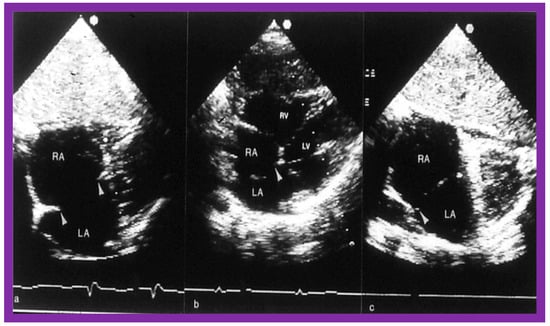

2. Diagnosis